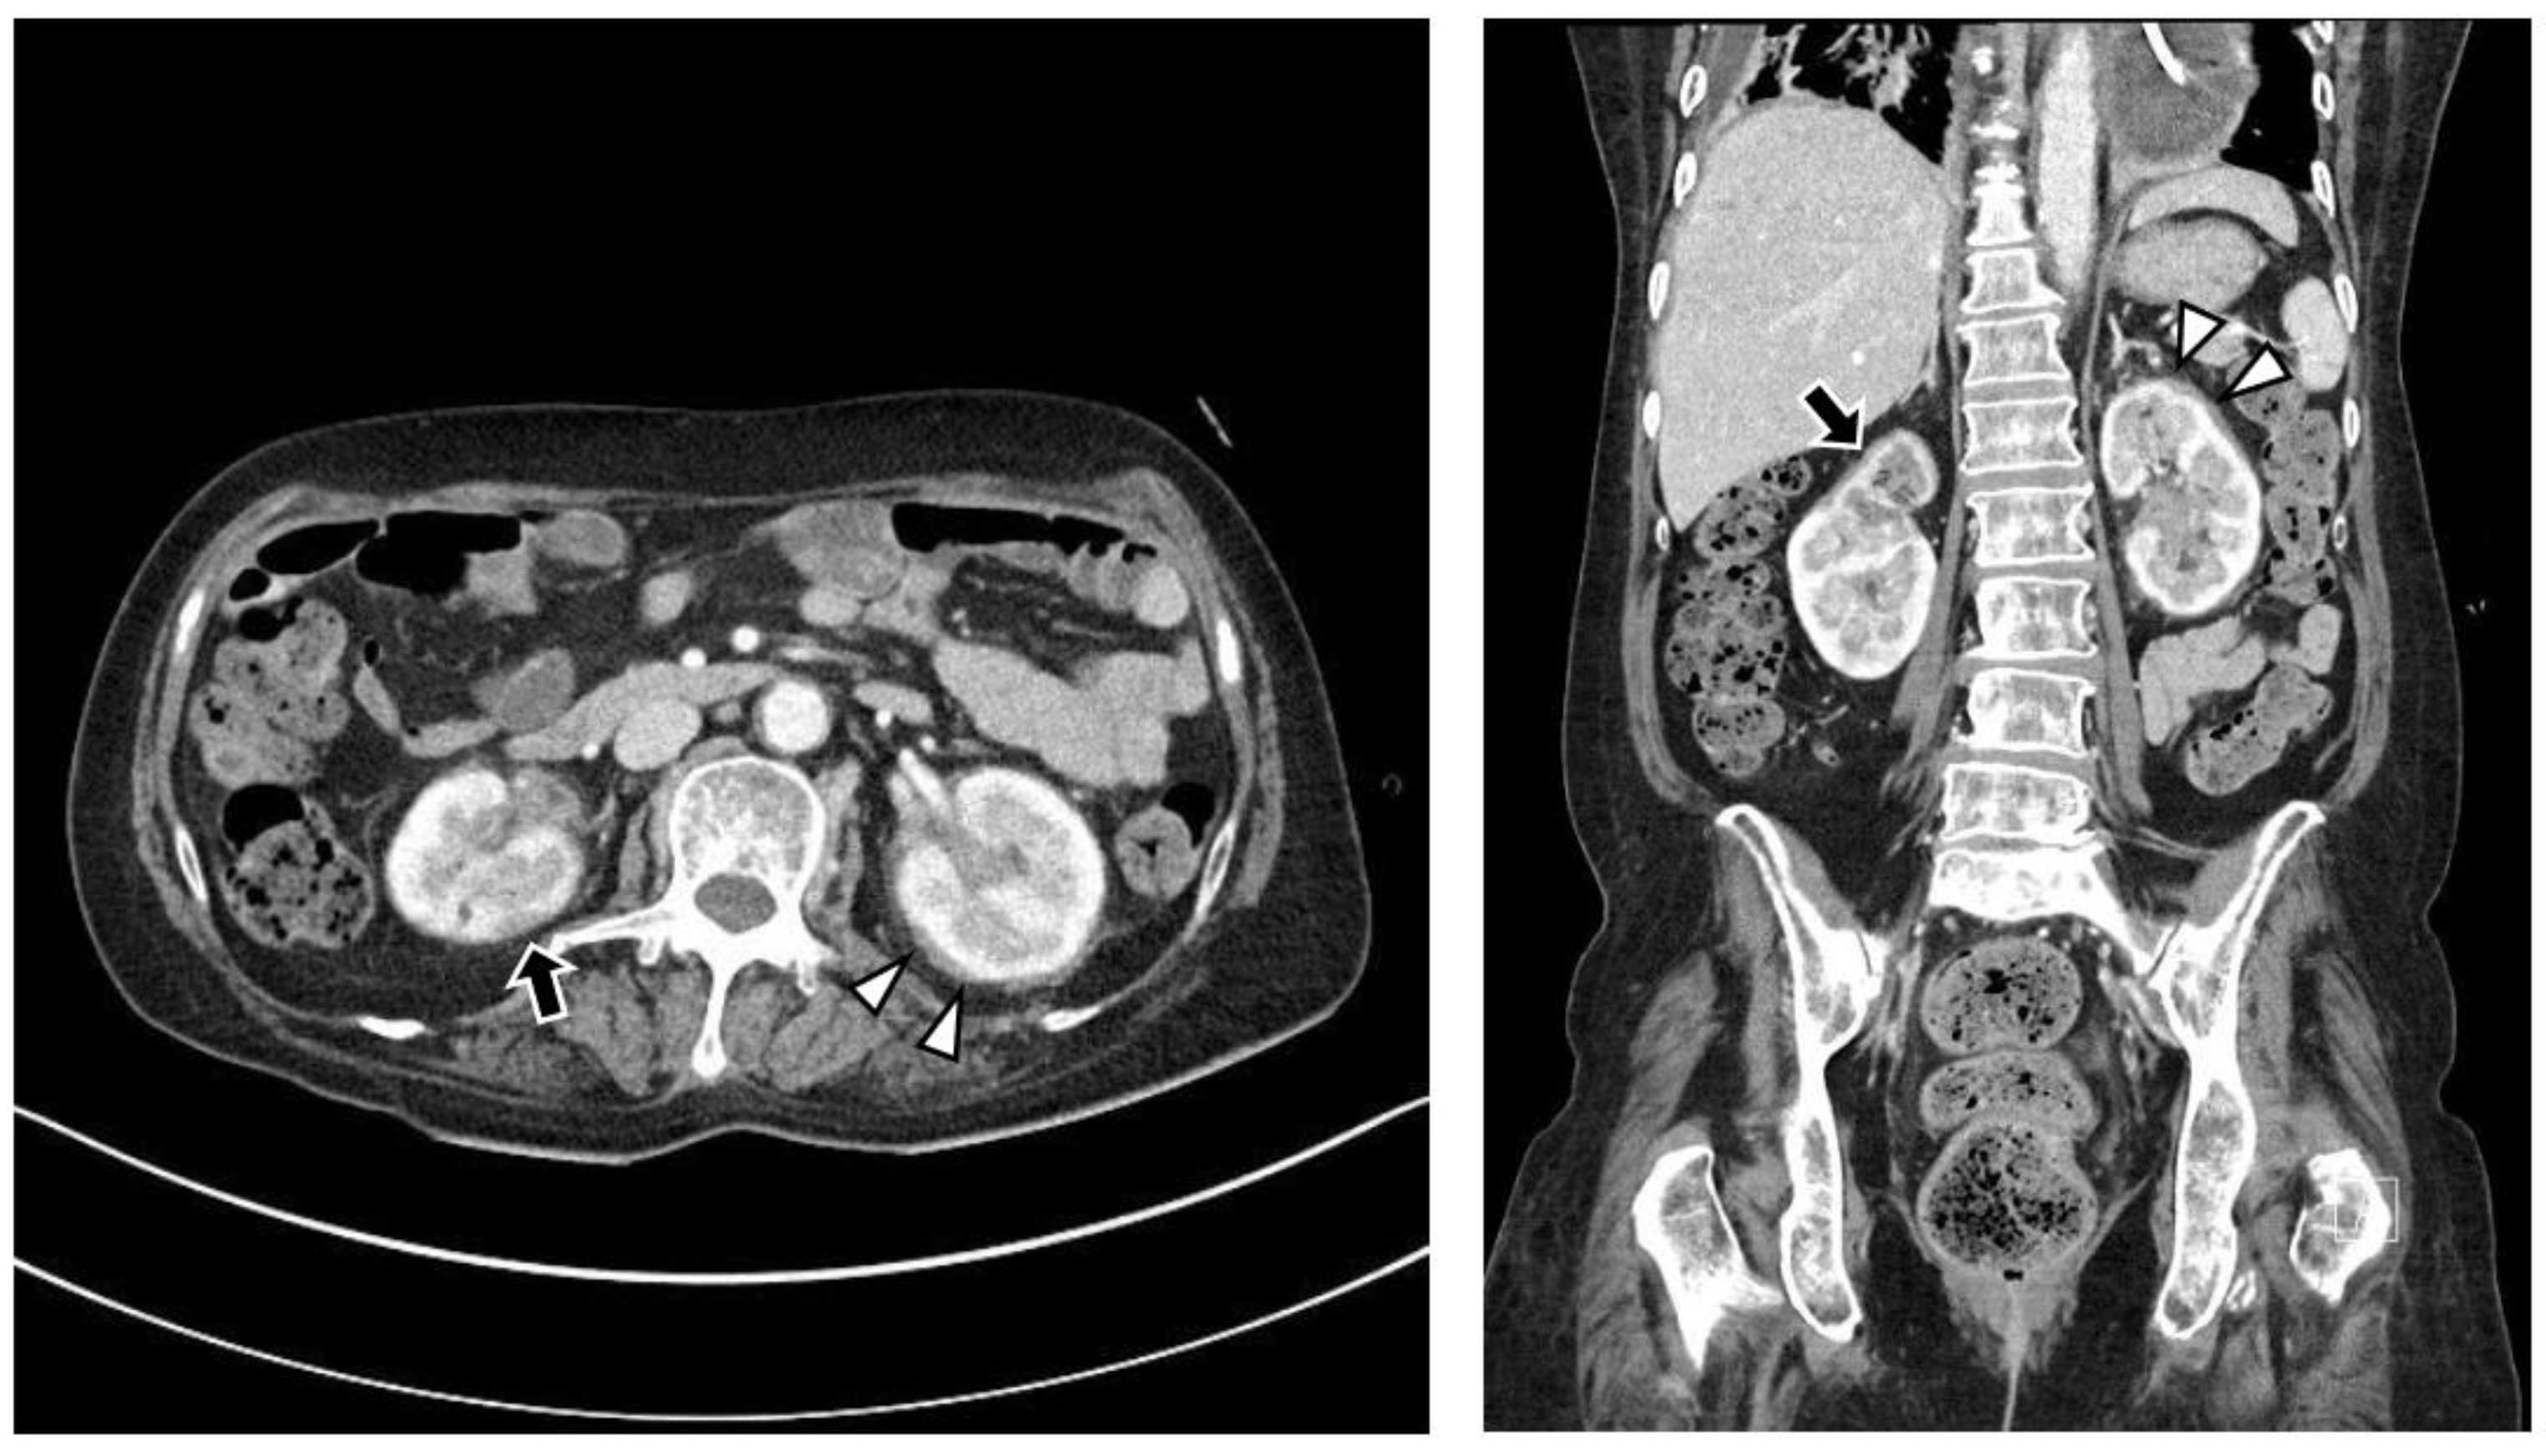

The chest CT showed notable pericardial effusion with pericardial enhancement and pleural effusion with pleural enhancement (Figure 2). The abdominal CT showed fluid collection in both perirenal spaces and diffuse infiltration in both kidneys (Figure 3). Pericardial biopsy revealed chronic active inflammation with nonspecific findings. The PET/CT showed increased uptake in the sacrum, distal femur, proximal tibia, and spleen, with pericardial and pleural effusion (Figure 4). The simple radiography and MRI of the left knee showed patchy sclerotic changes in the medulla of the distal femur and proximal tibia (Figure 1).

Figure 3.

Upon abdominal computed tomography, there is fluid collection in both perirenal spaces (white arrowheads) and cortical scarring in the upper pole of the right kidney (black arrows), which is sequelae of recurrent urinary tract infection of the right kidney. There are findings of diffuse renal involvement, which are non-specific findings of medical renal disease, but there is no evidence of distant metastasis.